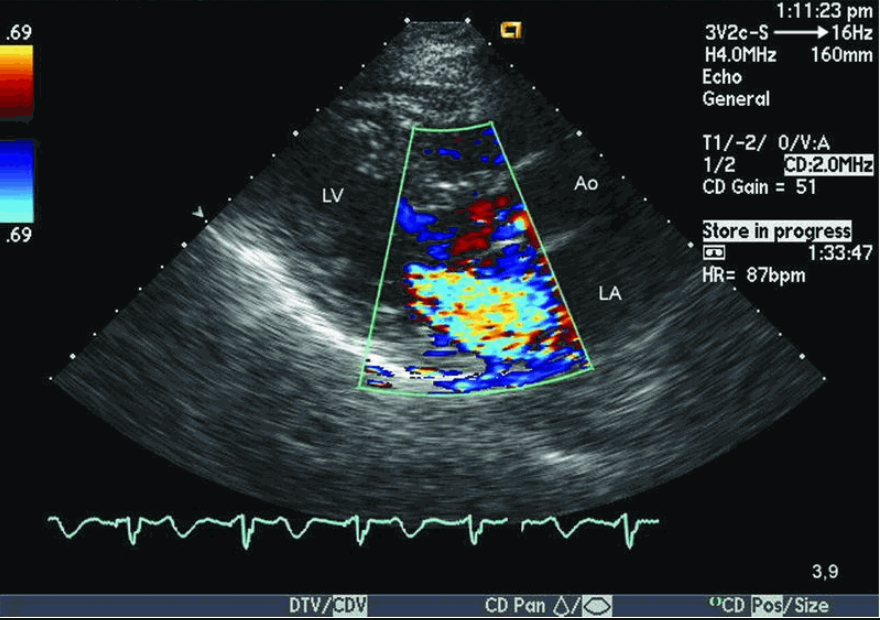

Siêu âm Doppler là loại siêu âm có độ chính xác cao nhất và hình ảnh siêu âm có màu dễ quan sát. Là một hình thức siêu âm hiện đại nhất hiện nay, siêu âm Doppler được sử dụng rộng rãi và ứng dụng trong nhiều trường hợp cụ thể. Đó là những trường hợp sau đây:

- Kiểm tra và phát hiện các vấn đề ở tim: khuyết van tim, hở van tim,…